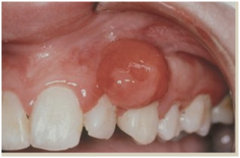

"pregnancy tumor" a)gingival hyperplasia b)papillary hyperplasia of the palate c)epulis fissuratum d)pyogenic granuloma

Front

pyogenic granuloma- granulation tissue in response to local irritant

Back